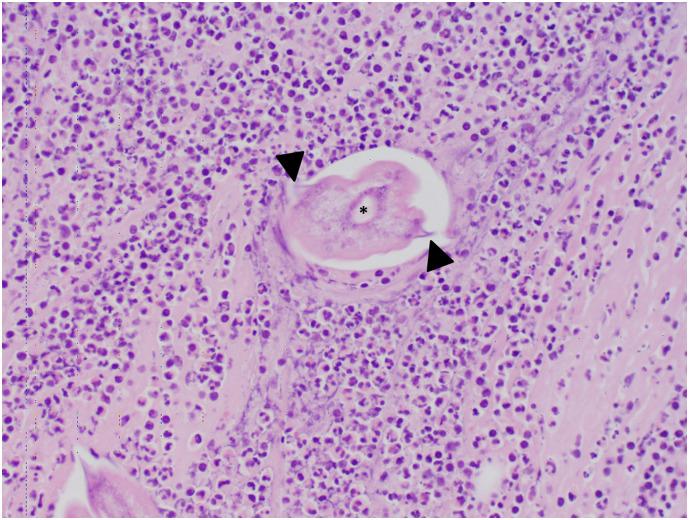

A group of 4-month-old beef calves were examined for clinical respiratory disease with labored breathing, coughing, and fevers of over 104°F. Necropsy of one of the calves revealed lungs that were not collapsed but had red mottled appearance on cut surface. Assessment of lung tissue by bacterial culture and PCR did not reveal bovine bacterial or viral respiratory pathogens. Histopathology of affected tissues and lymph nodes revealed larval ascarid nematodes. In combination with phylogenetic analysis, amplification and sequencing of ITS1 was used to identify the larvae as Ascaris.

对一群4月龄的肉用犊牛进行了检查,这些犊牛患有临床呼吸道疾病,表现为呼吸费力、咳嗽,体温超过104°F。对其中一头犊牛进行尸检,发现肺部未塌陷,但切开表面呈红色斑驳状。通过细菌培养和PCR对肺组织进行评估,未发现牛细菌性或病毒性呼吸道病原体。对受影响的组织和淋巴结进行组织病理学检查,发现了蛔虫幼虫。结合系统发育分析,利用ITS1的扩增和测序将幼虫鉴定为蛔虫。